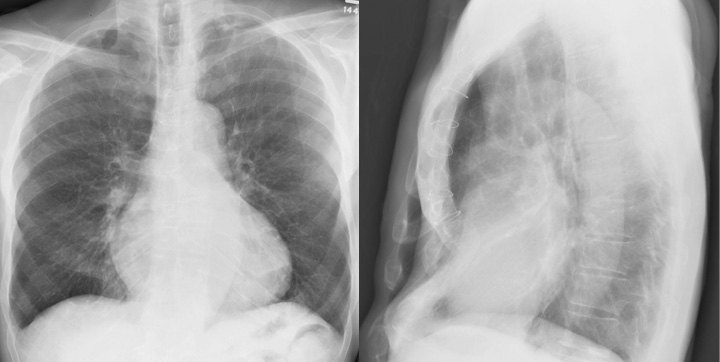

Pectus